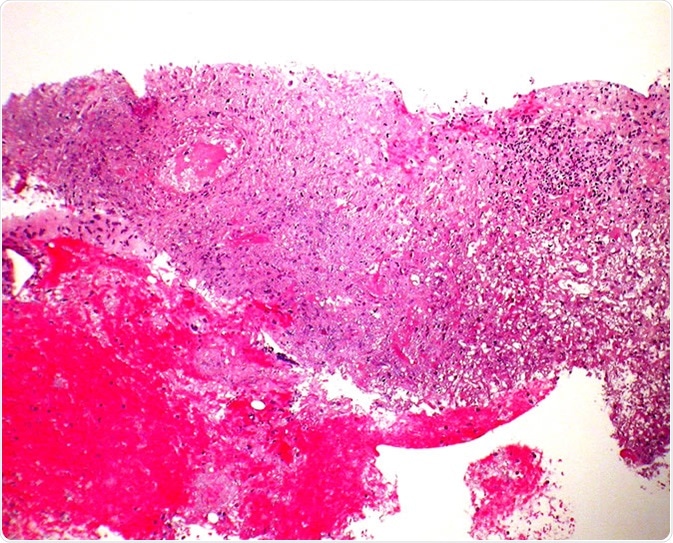

Granulomatosis with polyangiitis (GPA) - Core biopsy Case 190

Granulomatosis with polyangiitis (GPA) - Core biopsy Case 190" by Pulmonary Pathology is licensed under CC BY-SA 2.0